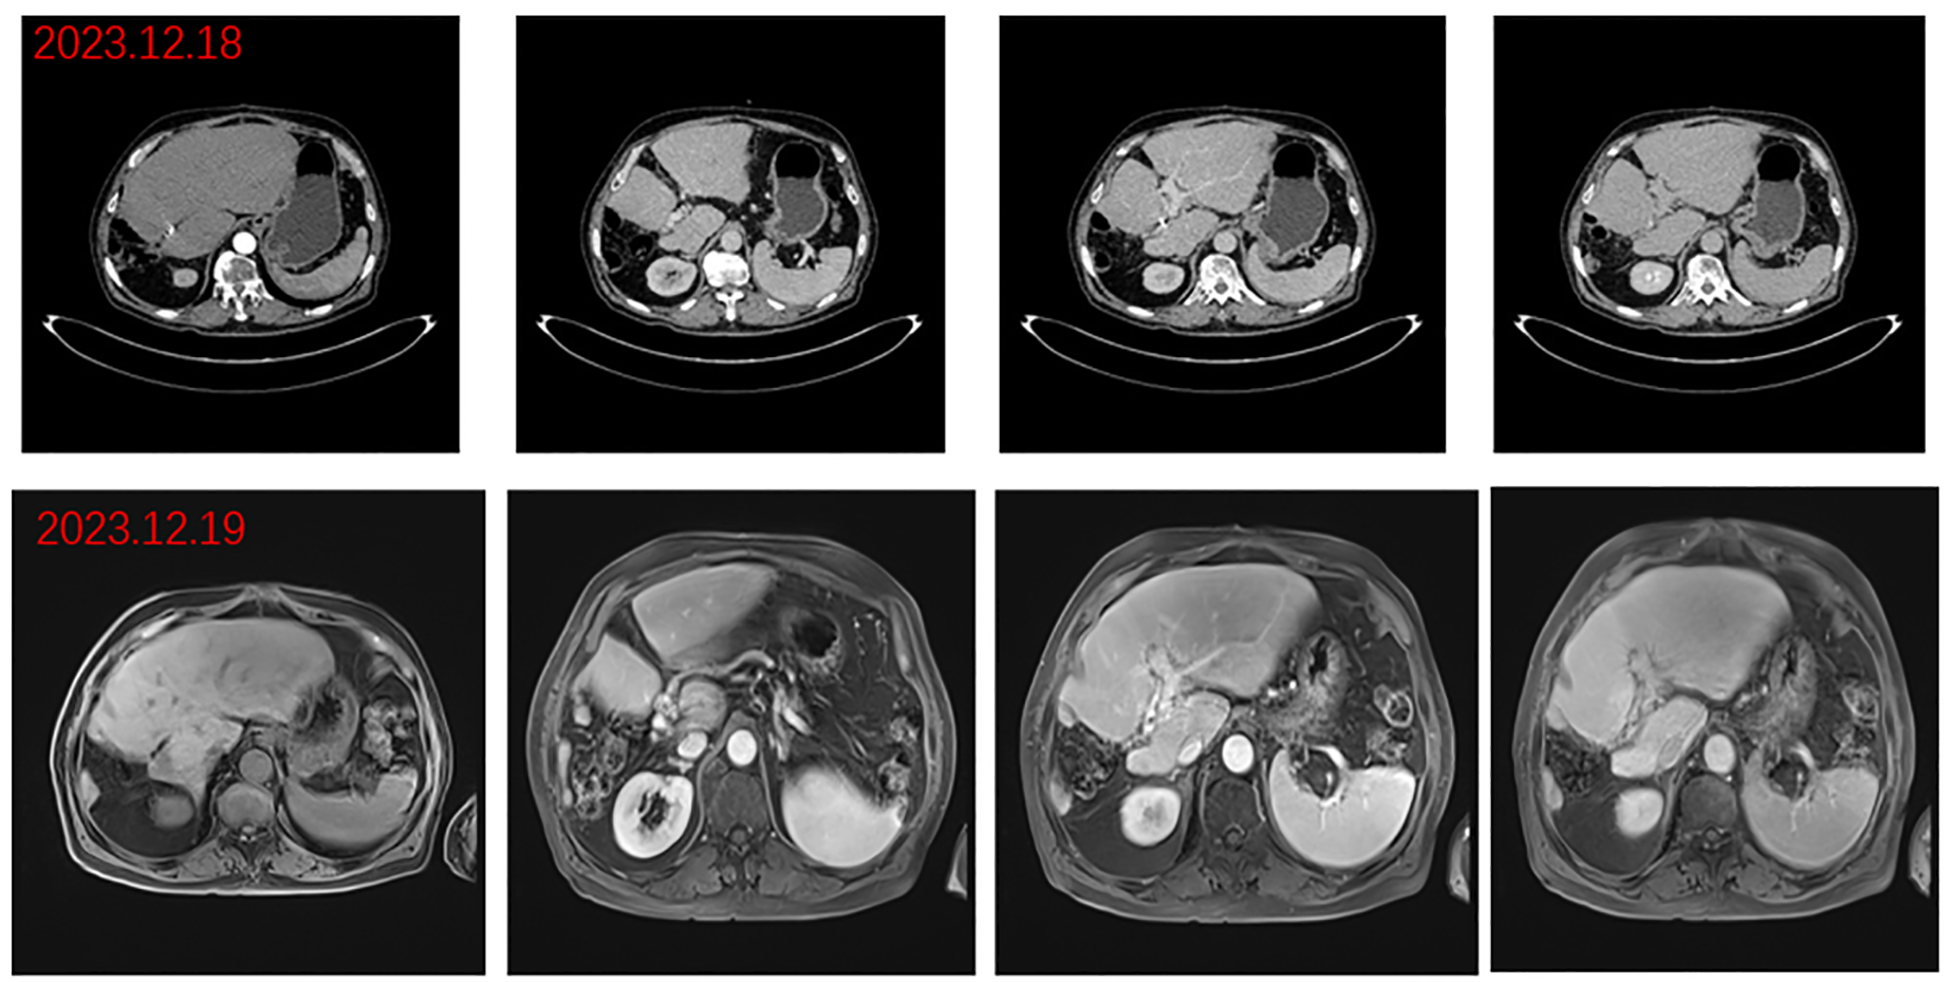

The patient was a 76-year-old male who presented to Lanzhou University First Hospital on August 5, 2021, with upper abdominal bloating and mild pain persisting for over one month. He reported no other symptoms, and an abdominal ultrasound conducted at another local hospital indicated the presence of a liver mass. His medical history included chronic hepatitis B for over 30 years, hypertension, diabetes, and cataract surgery with intraocular lens implantation. Upon physical examination, the patient exhibited normal skin and mucosal color without jaundice, a flat abdomen devoid of abdominal wall varices, and no remarkable gastrointestinal contour or peristalsis. There was no tenderness upon abdominal palpation, and the liver was palpable below the rib margin. Murphy’s sign was negative, and bowel sounds were noted at a rate of four times per minute. Laboratory tests revealed the following values within normal limits: white blood cell count (WBC: 5.03 × 10^9/L), neutrophil ratio (NEUT%: 68.8%), hemoglobin (HGB: 124 g/L), and platelet count (PLT: 205 × 10^9/L). Tumor markers were elevated, including alpha-fetoprotein (AFP: 289 U/mL), carbohydrate antigen 19-9 (CA 19-9: 109 U/mL), carcinoembryonic antigen (CEA: 1.4 ng/mL), and ferritin (519 ng/mL). Biochemical analysis indicated that aspartate aminotransferase (AST: 67 U/L), alanine aminotransferase (ALT: 216 U/L), total bilirubin (TBIL: 16.4 µmol/L), direct bilirubin (DBIL: 4.8 µmol/L), alkaline phosphatase (ALP: 216 U/L), gamma-glutamyl transferase (GGT: 371 U/L), and glucose (GLU: 6.59 mmol/L) were outside normal ranges. Tests for hepatitis B (2+, 5+) and hepatitis B virus DNA (HBV DNA < 100 IU/mL) were negative. Brain natriuretic peptide (BNP: 143.4 pg/mL) was outside the normal range. The enhanced abdominal CT scan revealed a large mass-like abnormal enhancement in the right lobe of the liver, suggesting hepatocellular carcinoma (HCC) with portal vein thrombosis in the main trunk as well as the left and right branches, cirrhosis, and portal hypertension (including esophageal and gastric fundus varices). Magnetic resonance imaging (MRI) of the liver revealed a large abnormally enhanced mass in the right lobe, suggesting hepatocellular carcinoma (HCC) with intratumoral hemorrhage and portal vein thrombosis in the main trunk as well as the left and right branches; cirrhosis, splenomegaly, a small amount of ascites, liver disease, and gallbladder disease (Figure 1). The patient was diagnosed with HCC of the right lobe, post-hepatitis B cirrhosis, grade 3 hypertension (very high risk), and type 2 diabetes, classified as stage IIIa according to the CNLC staging system (Figure 2). An initial multidisciplinary team (MDT) discussion resulted in a treatment plan that included hepatic artery infusion chemotherapy (HAIC) treatment (FOLFOX), combined with 200 mg sintilimab and sorafenib 0.4 g bid targeted therapy. The patient was discharged on August 16th, 2021. After discharge, oral sorafenib 0.4g bid targeted therapy was prescribed. On the second admission, a second MDT discussion was held to adjust the protocol: HAIC treatment and percutaneous liver puncture for radioactive 125I particle implantation, combined with 200 mg sintilimab and sorafenib targeted therapy. After the fifth admission, there was no significant change in the portal vein tumor thrombus. The third MDT was conducted, and on March 29, 2022, “percutaneous hepatic puncture radioactive 125I particle implantation” radiation therapy was performed. Additionally, because the patient could not tolerate bisphosphonates, the treatment was changed to once-daily targeted therapy with 8 mg of lenvatinib. The patient underwent abdominal CT (plain + enhanced) at the sixth admission on June 21, 2022, compared with the previous scan on March 28, 2022 showed a lesion in the right lobe of the liver with little change, along with occlusion of the main portal vein and portal spongiosis, which remained little changed from the previous scan (Figure 2). After comprehensive consideration of the timing of surgical resection following successful conversion, the decision was made to perform surgical treatment. Subsequently, another preoperative evaluation was conducted, which included gastroscopy, revealing a 0-Ia+IIc type lesion can be seen near the anterior wall of the cardia, with a size of about 3 × 2 cm and chronic atrophic gastritis (Figure 3A). After the fourth MDT, the gastric tumor was initially resected via laparoscopy combined with endoscopy under general anesthesia on July 4, 2022 (endoscopic mucosal resection, partial gastrectomy, and D1 lymph node dissection). Due to the patient’s poor cardiopulmonary function during the operation, the laparoscopic surgery was interrupted and converted into an open procedure for right hepatectomy and cholecystectomy (Figure 3B). The postoperative gastric histopathology report indicated ectopic hyperplasia of adenoepithelial hyperdifferentiated epithelial endothelium and focal carcinomatous lesions (Figure 3C). Two trans arterial chemoembolization (TACE) procedures were performed on September 13, 2022, and April 3, 2023, as adjuvant treatment following hepatic resection, in accordance with the Guidelines for the Diagnosis and Treatment of Primary Hepatocellular Carcinoma (2022 edition). Postoperative abdominal CT and MRI were performed on December 18, 2023, which revealed the disappearance of the portal vein thrombus and widening of the hepatic fissure (Figure 4). Remarkably, the patient demonstrated a favorable prognosis, recovering well and remaining free of tumor recurrence or metastasis during over eight months of follow-up.

Figure 4

Postoperative images. Arterial, portal, and delayed phase CT: disappearance of portal cancer embolus and resection of right lobe lesion and portal phase, delayed phase abdominal MR.